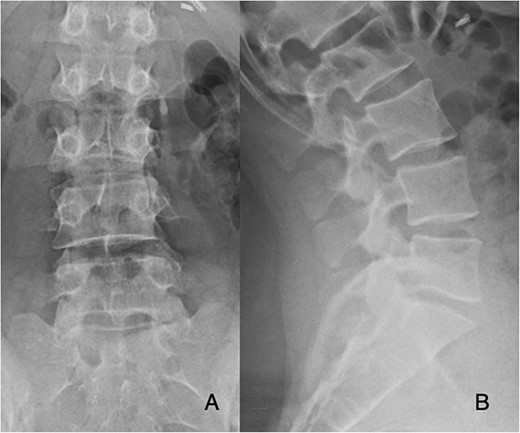

Preoperatively, her physical exam demonstrated left-sided quadriceps weakness and minimally diminished sensation in an L3-L5 distribution. The patient’s magnetic resonance imaging (MRI) demonstrated degeneration of the L5-S1 disc with disc height loss and left-sided L5-S1 foraminal stenosis (Figs 1 and 2).

Preoperative PA and lateral films demonstrate decreased disc height at L5-S1.